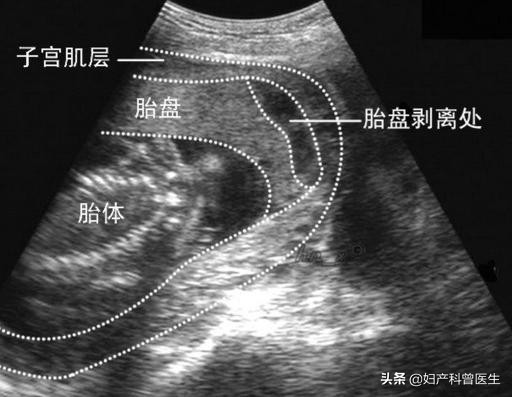

胎盘早剥

胎盘早剥B超图